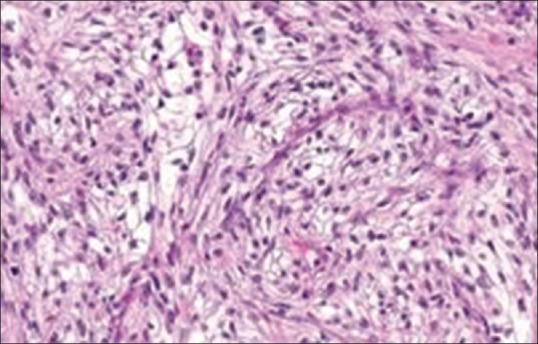

具有肉瘤样特征的肾细胞癌是一种罕见的表现,发病率为5%。肉瘤样肾细胞癌通常伴有不良预后。它通常转移到肺、骨和肝。伴有副肿瘤综合征的皮肤病表现极为罕见。肾细胞癌中PNP的发病机制尚不清楚;然而,迄今为止,很少有文献报道针对一组plakin家族的抗体,该家族在RCC的中间丝附着中起关键作用。我们报告一例64岁女性肾细胞癌合并PNP病例。

Renal cell carcinoma with sarcomatoid features is a rare presentation with a 5% incidence. Sarcomatoid renal cell carcinoma is usually associated with poor prognosis. It commonly metastasizes to the lungs, bones, and liver. Dermatological manifestation with paraneoplastic syndrome is extremely rare. Pathogenesis of PNP in renal cell carcinoma is not cleat; till date, however, few literature suggest antibodies against a group plakin family which plays a key role in intermediate filament attachment in RCC. We present PNP in a 64-year-old female associated with renal cell carcinoma.